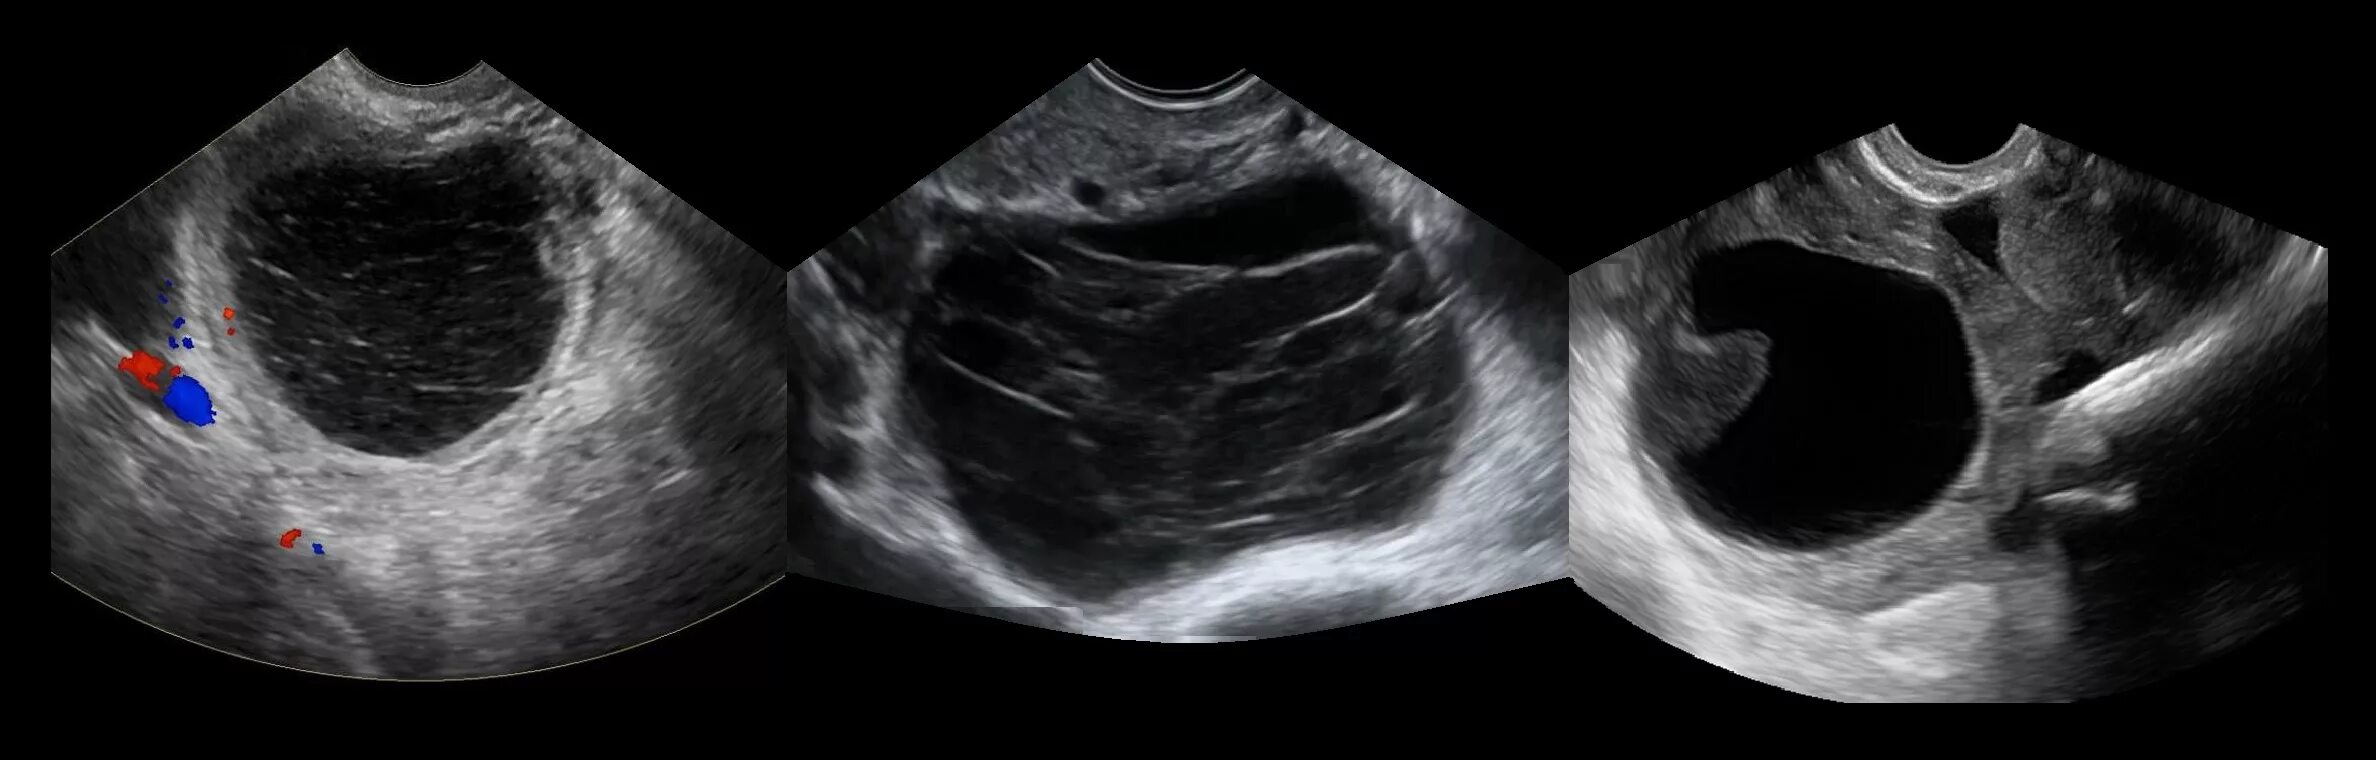

Как выглядит яичник